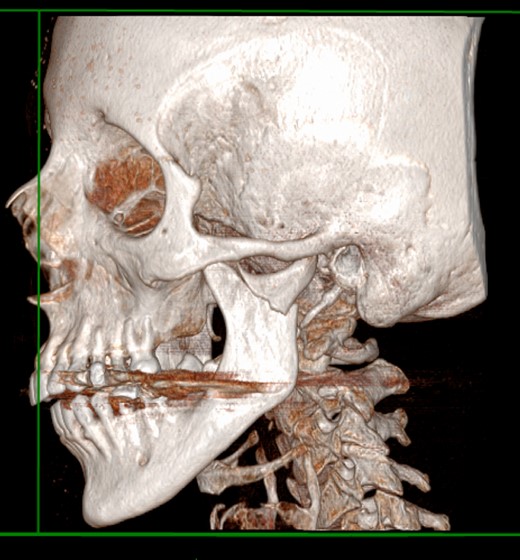

At the admission, the patient underwent a CT scan, the left mandibular subcondylar fracture was diagnosed (Fig. 1) and open reduction and rigid fixation was programmed.